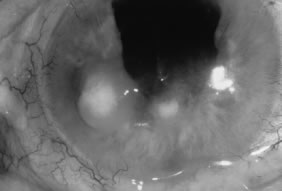

Candida infection typically produces epithelial ulceration, focal necrotizing stromal inflammation, moderate cellular infiltrate and edema in the adjacent stroma, and mild or moderate iritis in the early stages, indistinguishable from bacterial keratitis (Figs. 15, 16, and 17). Fungal elements cannot be detected by biomicroscopy. If untreated, the keratitis evolves to produce dense suppuration and necrosis of the deep stroma. Although multifocal suppuration may develop in polymicrobial keratitis, there is no distinctive sign of mixed Candida and bacterial infection (Fig. 18).

Fig. 15. C. albicans keratitis in an eye following chronic use of corticosteroid drops for herpes simplex keratitis. Note the central suppuration and perforation, endothelial plaques, and hypopyon.